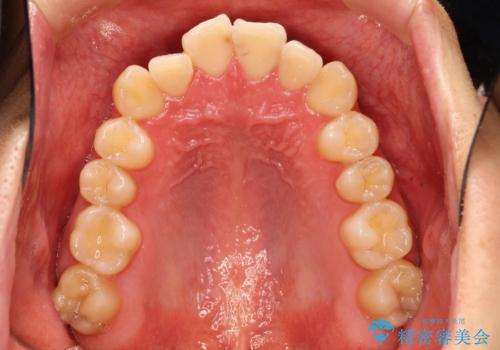

- 前歯の凸凹を主訴に来院された患者様です。

インビザラインにて治療を行いました。